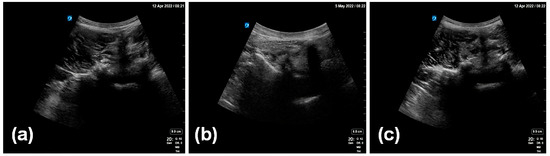

Figure 2. Examples of collected ultrasound images (ac).

In this study, the clinical data were collected from 300 patients. Most of these patients suffered from lower back pain and were undergoing pain treatment at the Department of Anesthesiology of Peking Union Medical College Hospital (PUMCH), Chinese Academy of Medical Sciences. The study protocol was numbered K22C2241 and approved by the Ethics Review Committee of PUMCH. All the patients received ultrasound scanning before and after pain treatment. The ultrasound images were captured by one or two expert sonographers using a SonoSite X-Porte scanner (Fujifilm, Tokyo, Japan), with a 2–5 MHz curved-array transducer (C60xp/5-2), a scanning depth of 7 cm, and a gain of 50%. The pixels of the original images in this study were 960 × 720. The collected data had the same scanning angle and a similar scanning field (Figure 2).